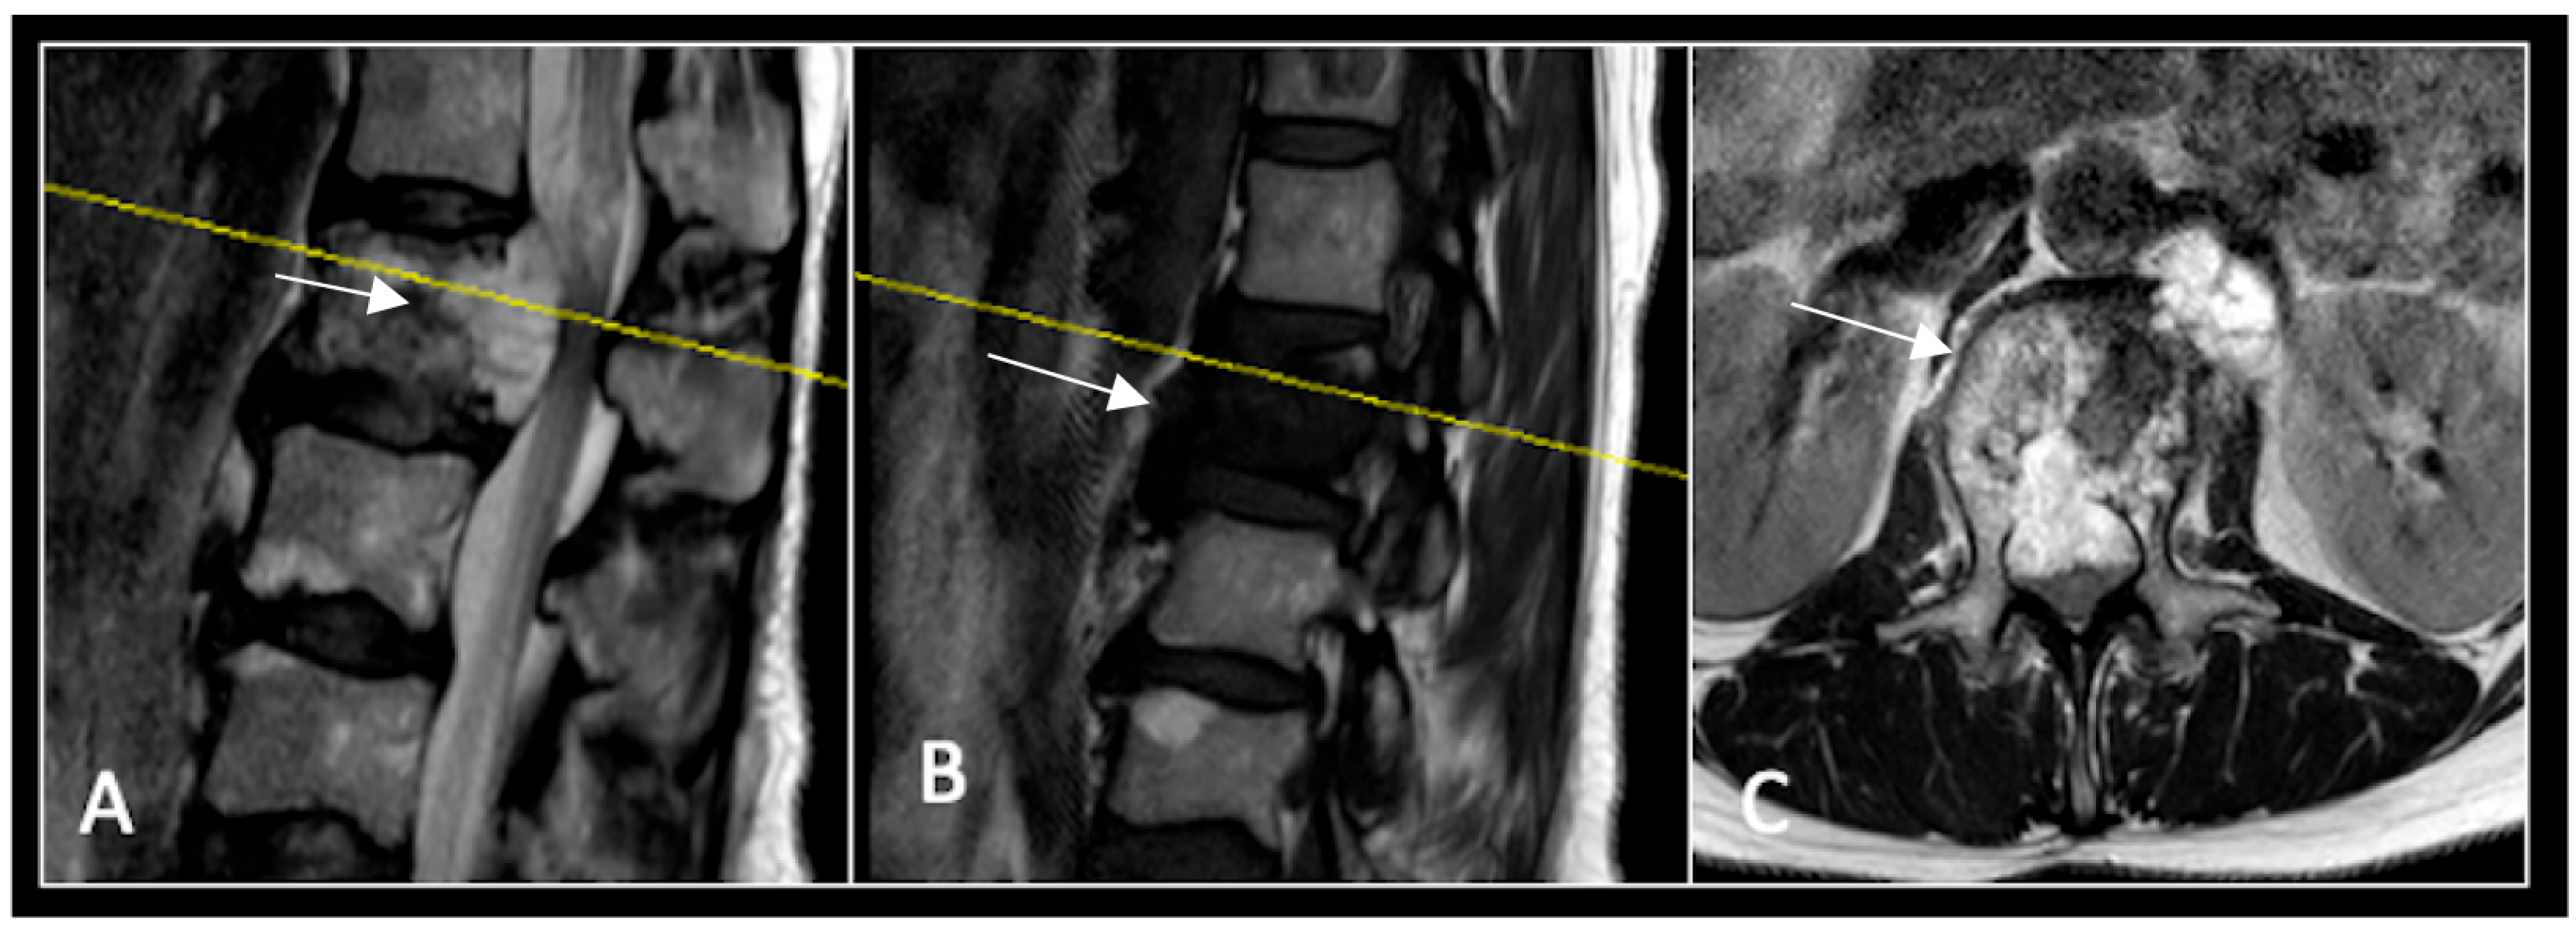

Figure 2.

MRI demonstrating a destructive lobular lesion localised to the C2 vertebra (chordoma) (arrow). There is significant left-sided extension into the paravertebral tissues laterally and epidural space centrally with indentation of the cord. The yellow line on the sagittal images denotes the level at which the corresponding axial section was obtained. (A) T2-W sagittal; (B) T1W sagittal; (C) T2W axial.